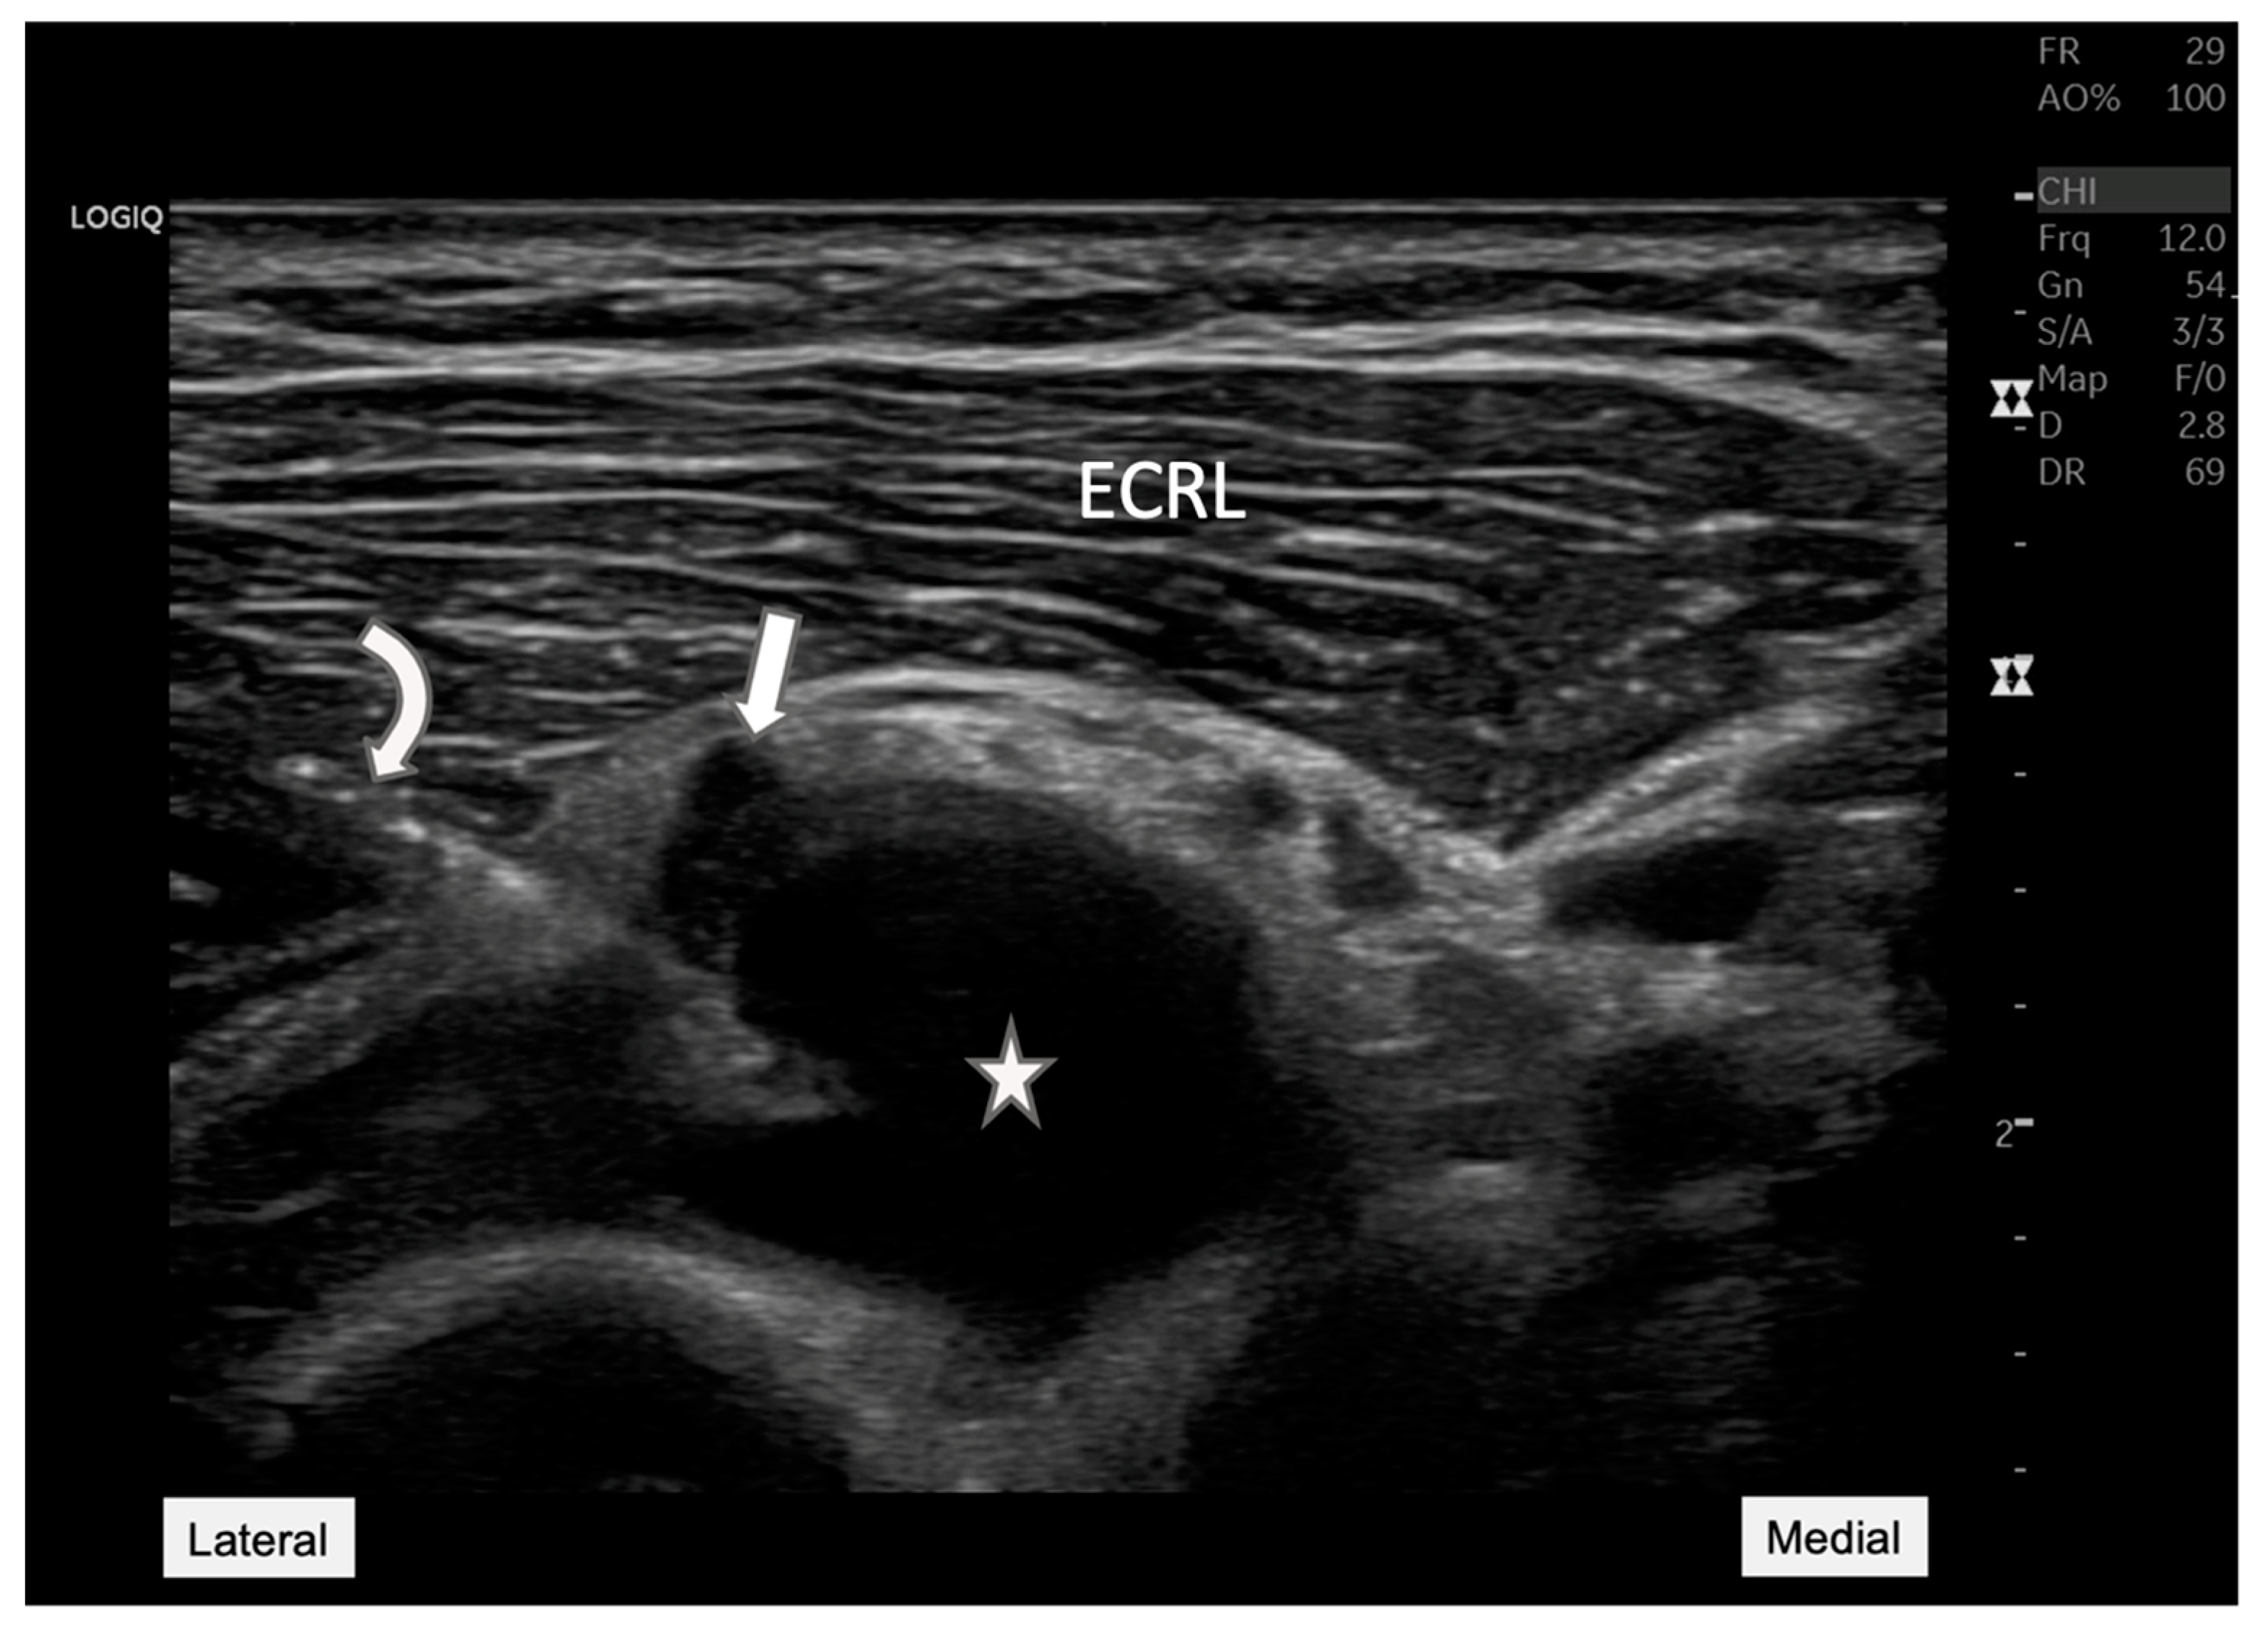

Figure 2.

Radial nerve entrapment at the Arcade of Frohse. Longitudinal ultrasound view of the posterior interosseous nerve (arrow) depicting the nerve compression at the Arcade of Frohse (arrowhead). The nerve is visibly constricted by an underlying anechoic cyst (star). This image demonstrates the value of ultrasound in visualizing soft tissue structures, providing essential diagnostic insights into the mechanisms of neuropathic pain and potential therapeutic targets. ECRL: Extensor carpi radialis longus.

Figure 1). The longitudinal ultrasound view of the radial nerve (

Figure 2) illustrates the entrapment of the posterior interosseous nerve (PIN), as it courses through the Arcade of Frohse. Notable compression of the nerve was seen due to an underlying anechoic cyst, which contributes significantly to the PIN’s entrapment at this anatomical site. The cyst’s proximity to the nerve and its effect on the nerve’s appearance and function are critical for diagnosing radial nerve compression. Additionally, nerve tracking to the supinator level also showed distinct hypoechogenicity and swelling of the PIN as it passed through the supinator muscle on the affected side, highlighting the pathological changes consistent with radial nerve compression (